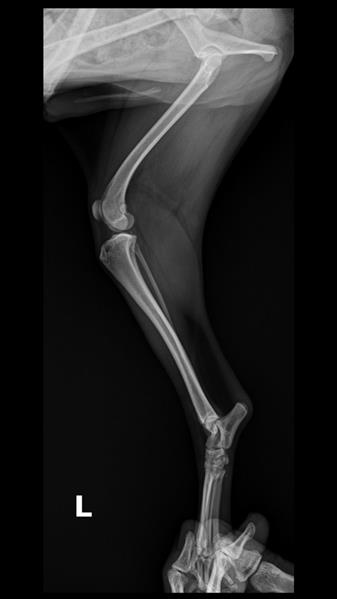

정확한 것은 임상증상도 확인하고, 촉진검사 등이 함께 필요하지만, 우선 올려주신 엑스레이 사진으로만 봤을 때 RT후지 대퇴골두 이형성 소견이 보입니다. 대퇴골두 제거수술이 필요할 것으로 보입니다.